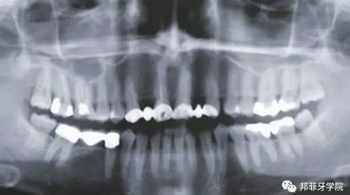

26歲女性患者,雙側(cè)上頜側(cè)切牙先天缺失,對(duì)原有修復(fù)體的“形態(tài)”、“光澤”等方面不滿(mǎn)意,希望重新修復(fù)(圖1&2)。12及22原為粘接橋修復(fù),11根管治療史;拆除原修復(fù)體后余鄰牙完整,未見(jiàn)病理性探診深度。無(wú)系統(tǒng)疾病史?;颊咂谕递^高,告知治療流程佩戴臨時(shí)卡環(huán)義齒等(圖3)、費(fèi)用、風(fēng)險(xiǎn)后表示接受治療。

圖2:治療前全景片